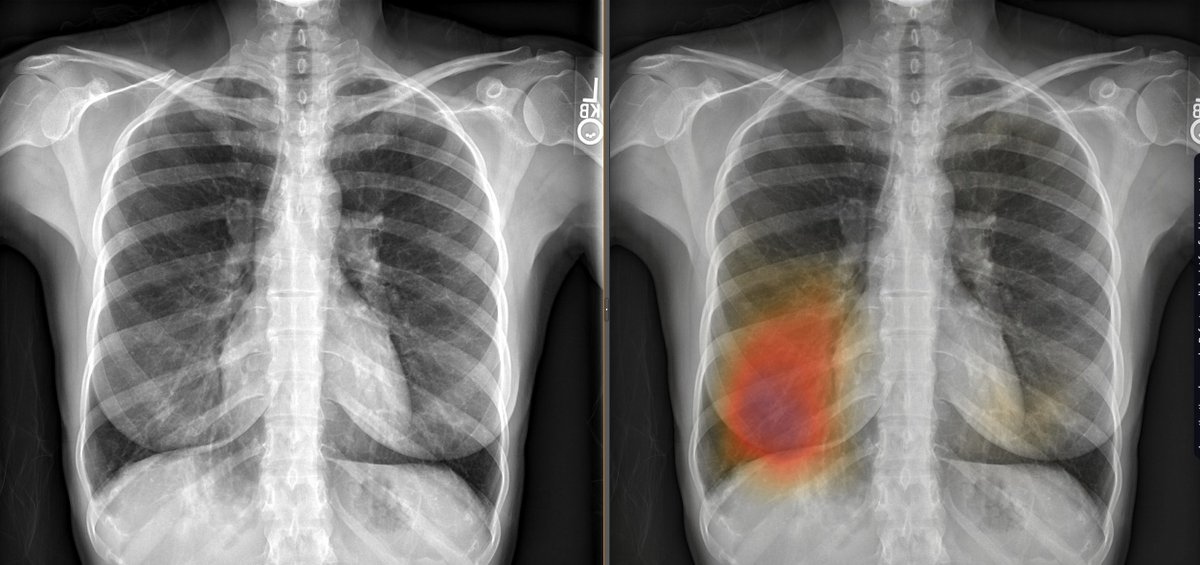

For #ImagingAI algorithms to work in clinical practice, they need to be designed to function in many contexts. I'm still amazed by #radres @BJHurtMD's algorithm via @ArterysInc, still working hard 😎, detecting pneumonia beyond #covid (CT-confirmed). journals.lww.com/thoracicimagin…

For #ImagingAI algorithms to work in clinical practice, they need to be designed to function in many contexts. I'm still amazed by #radres @BJHurtMD's algorithm via @ArterysInc, still working hard 😎, detecting pneumonia beyond #covid (CT-confirmed). journals.lww.com/thoracicimagin…